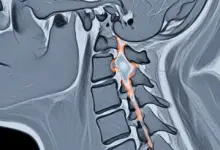

- Tomografia: detalha ossificações, osteófitos e calcificações discais.

- Radiografias: ajudam a avaliar alinhamento e curvatura cervical.